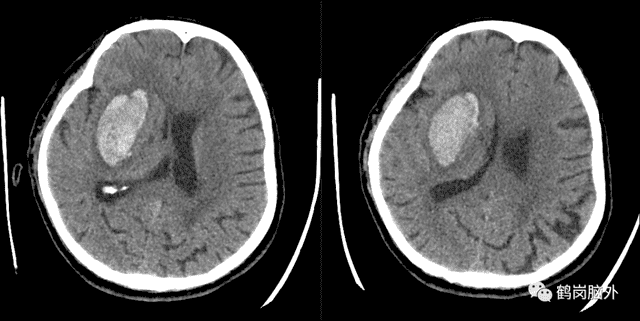

71岁的周先生突发左侧肢体不能活动来医院,头部CT检查发现脑出血,20多毫升的出血量不会危及生命,但左侧肢体无法活动,考虑到促进肢体功能的恢复,进行了3D打印技术脑出血微创手术治疗。术后3天可以在家人扶持下走路。

△可以看到出血量20余毫升,但脑室明显受压。

△3D打印的导板可以精确直达血肿中心。